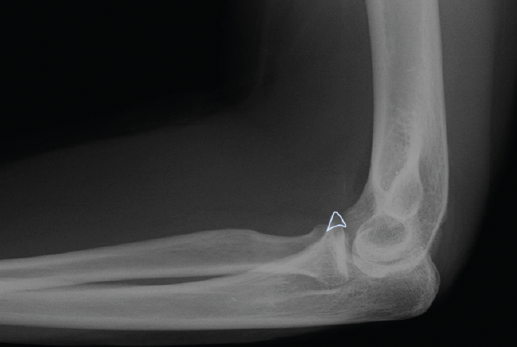

Qué se ve en la imagen?

Fractura de la coronoides